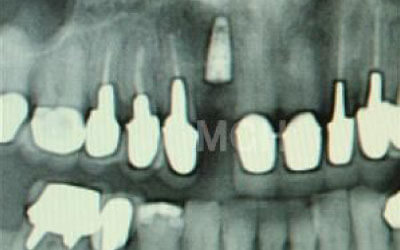

ブリッジなどの治療では前後の歯を大きく削る必要があります。場合によっては、虫歯でもないのに歯の神経をとることも。実は神経をとって被せ物をすると、歯は一気に最終ステージになってしまいます。

しかしインプラント治療なら、前後の歯を削る必要も神経をとる必要もありません。歯の寿命を延ばす上でも、健康な歯をできるだけ削らないのはとても大切なことなのです。

理由は、ブリッジをするために前後の歯を大きく削る必要があるからです。

場合によっては神経を取ることもあります。

それだけ歯にダメージを与えるので、その歯の寿命は一気に短くなります。

ブリッジは、抜けた部分の前後の歯を大きな虫歯の時と同じ位まで歯を削ります。

また、抜けた部分の歯の力を前後の歯が支えているため 常に1.5倍の力がブリッジの支えの歯にかかっています。

1)ブリッジ

2)歯を大きく削る+支えの歯に1.5倍の力がかかる

3)前後の歯の寿命が著しく減る

ブリッジの支えの歯は、データでは10年以内に68%が抜歯になります。